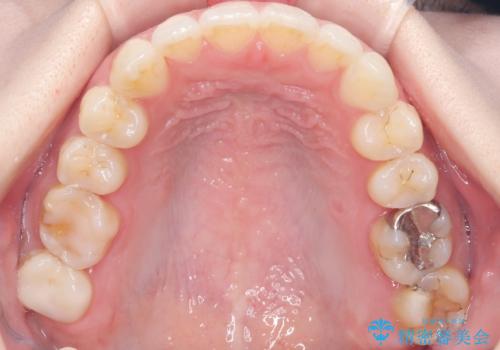

- 歯並びの乱れを改善したいと来院されました。精密検査の結果、犬歯を奥へ動かすことで、より美しい口元と安定した咬み合わせが得られると診断。患者様のご希望から、目立ちにくい審美ワイヤー矯正を採用し、効率的な歯の移動のために**リンガルアーチとTAD(矯正用アンカースクリュー)**を併用する計画を立てました。これにより、抜歯せずにスペースを確保し、犬歯をスムーズに遠心へ移動させます。

今回の矯正では、装置が目立たないよう透明なブラケットと白いワイヤーを使用。さらに、効率的な歯の移動のために、歯の裏側にリンガルアーチを設置しました。また、確実な奥歯の移動のために**TAD(矯正用アンカースクリュー)**を一時的に使用。これにより、犬歯を狙った位置へ正確に動かすことが可能に。目立ちにくい装置で快適に過ごしながら、理想的な歯並びと咬み合わせを獲得していただけました。